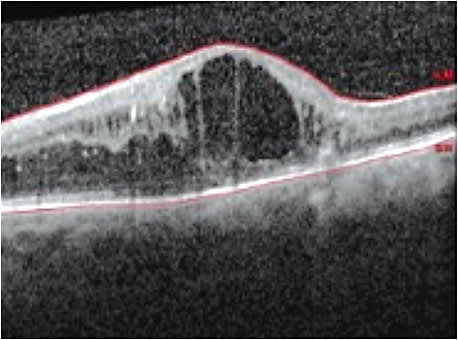

After repeated Ozurdex injections that result in improving either the VA or decreasing central macular thickness on OCT, one may want to consider longer acting, sustained-release implants, such as fluocinolone.

Patients should be closely monitored for increases in IOP, glaucoma, cataract formation and retinal detachment. The good news regarding the latter: Cutting-edge diagnostic technology, such as SD-OCT, OCTA, wide-field imaging and fundus autofluorescence, can aid us in detecting possible recurrence and, therefore, refer the patient back to the ophthalmologist for further intervention. OM